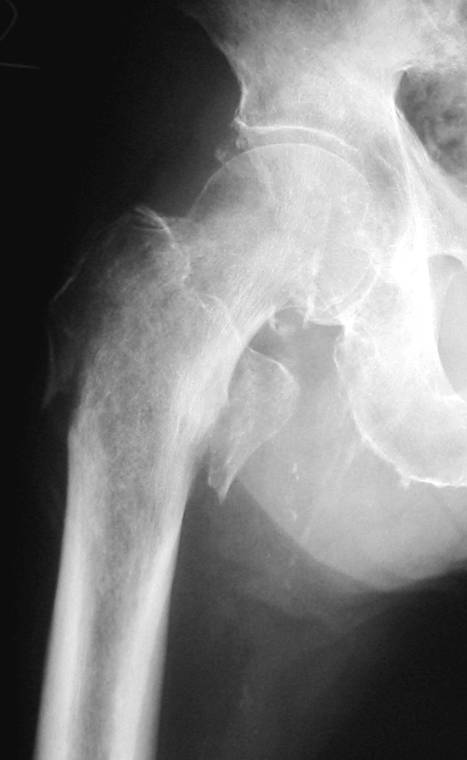

Radiography of the hip demonstrated avulsion of the lesser trochanter and fracture of the greater trochanter with no apparent intertrochanteric extension (Fig. 1). The fracture condition was well revealed by the CT scan (Fig. 2). MRI showed no typical abnormality at the intertrochanteric lesion (Fig. 3). Laboratory data including full blood cell count were normal. NTX/CR was normal. DEXA scan of vertebral bones showed a bone density 0.925 g/cm2, which is 88% of the means Japanese young adults.

Fig. 1 Anteroposterior radiograph of right hip on the day of injury